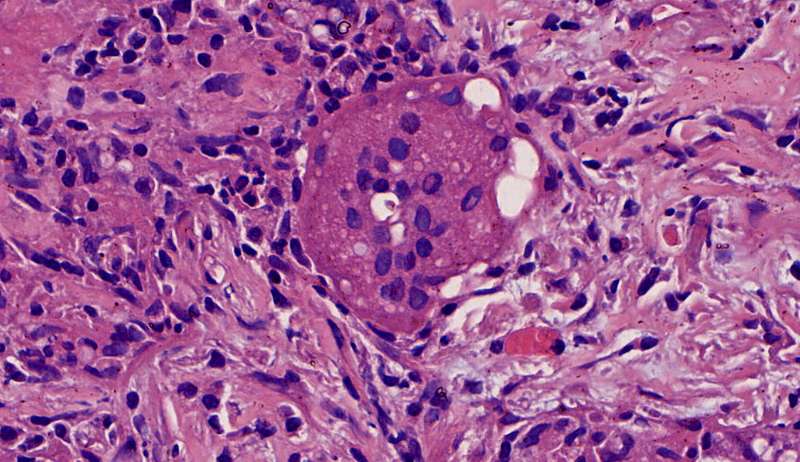

第二例隐球菌

整体是个类圆形,边界模糊(有晕征的感觉),肉芽肿一般都这样 里面也能见到许多小白球,大小从3微米到20微米不等 红细胞直径5-6微米 普通小淋巴细胞直径5微米 这里淋巴细胞挺多 有许多淋巴细胞,成堆

多核巨噬细胞吞了许多隐球菌 经常是反包围的感觉